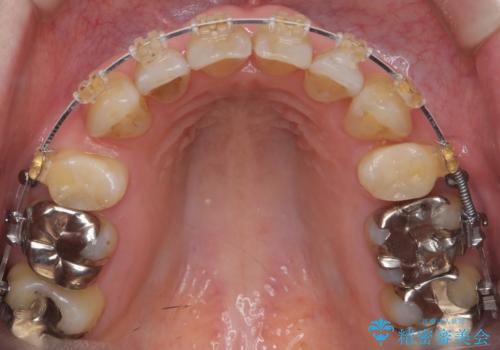

- 審美装置

- 3年3ヶ月

- 10-30回

叢生も著しく、少し年齢が上がってからの矯正治療となり、結果ブラックトライアングルが出てしまいましたが、並びの改善で非常に満足していただけました。